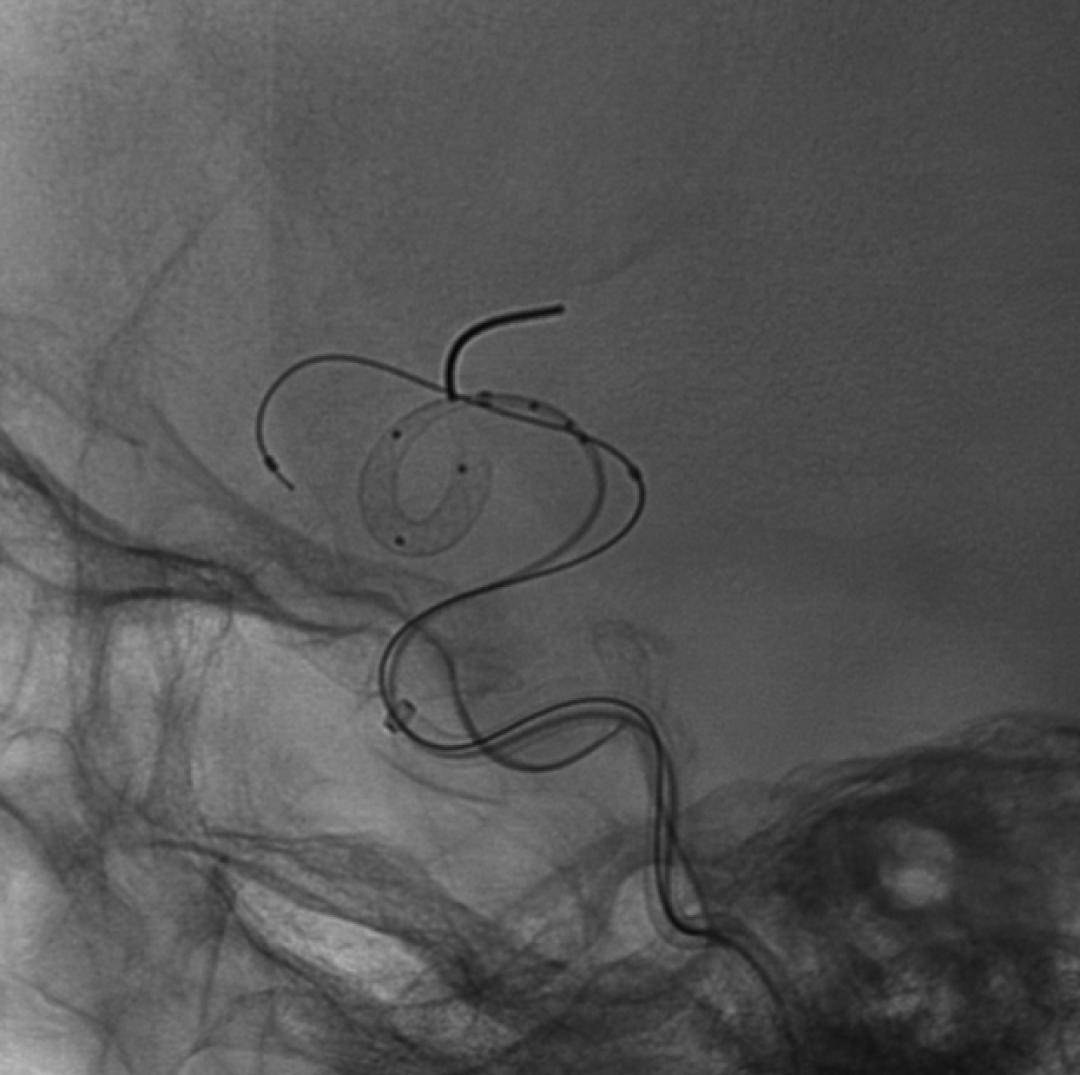

术后即刻造影

术后即刻造影,正侧位造影示载瘤动脉血流通畅,各主要分支血管显影良好,动脉瘤仅余部分少量显影。

术后CT